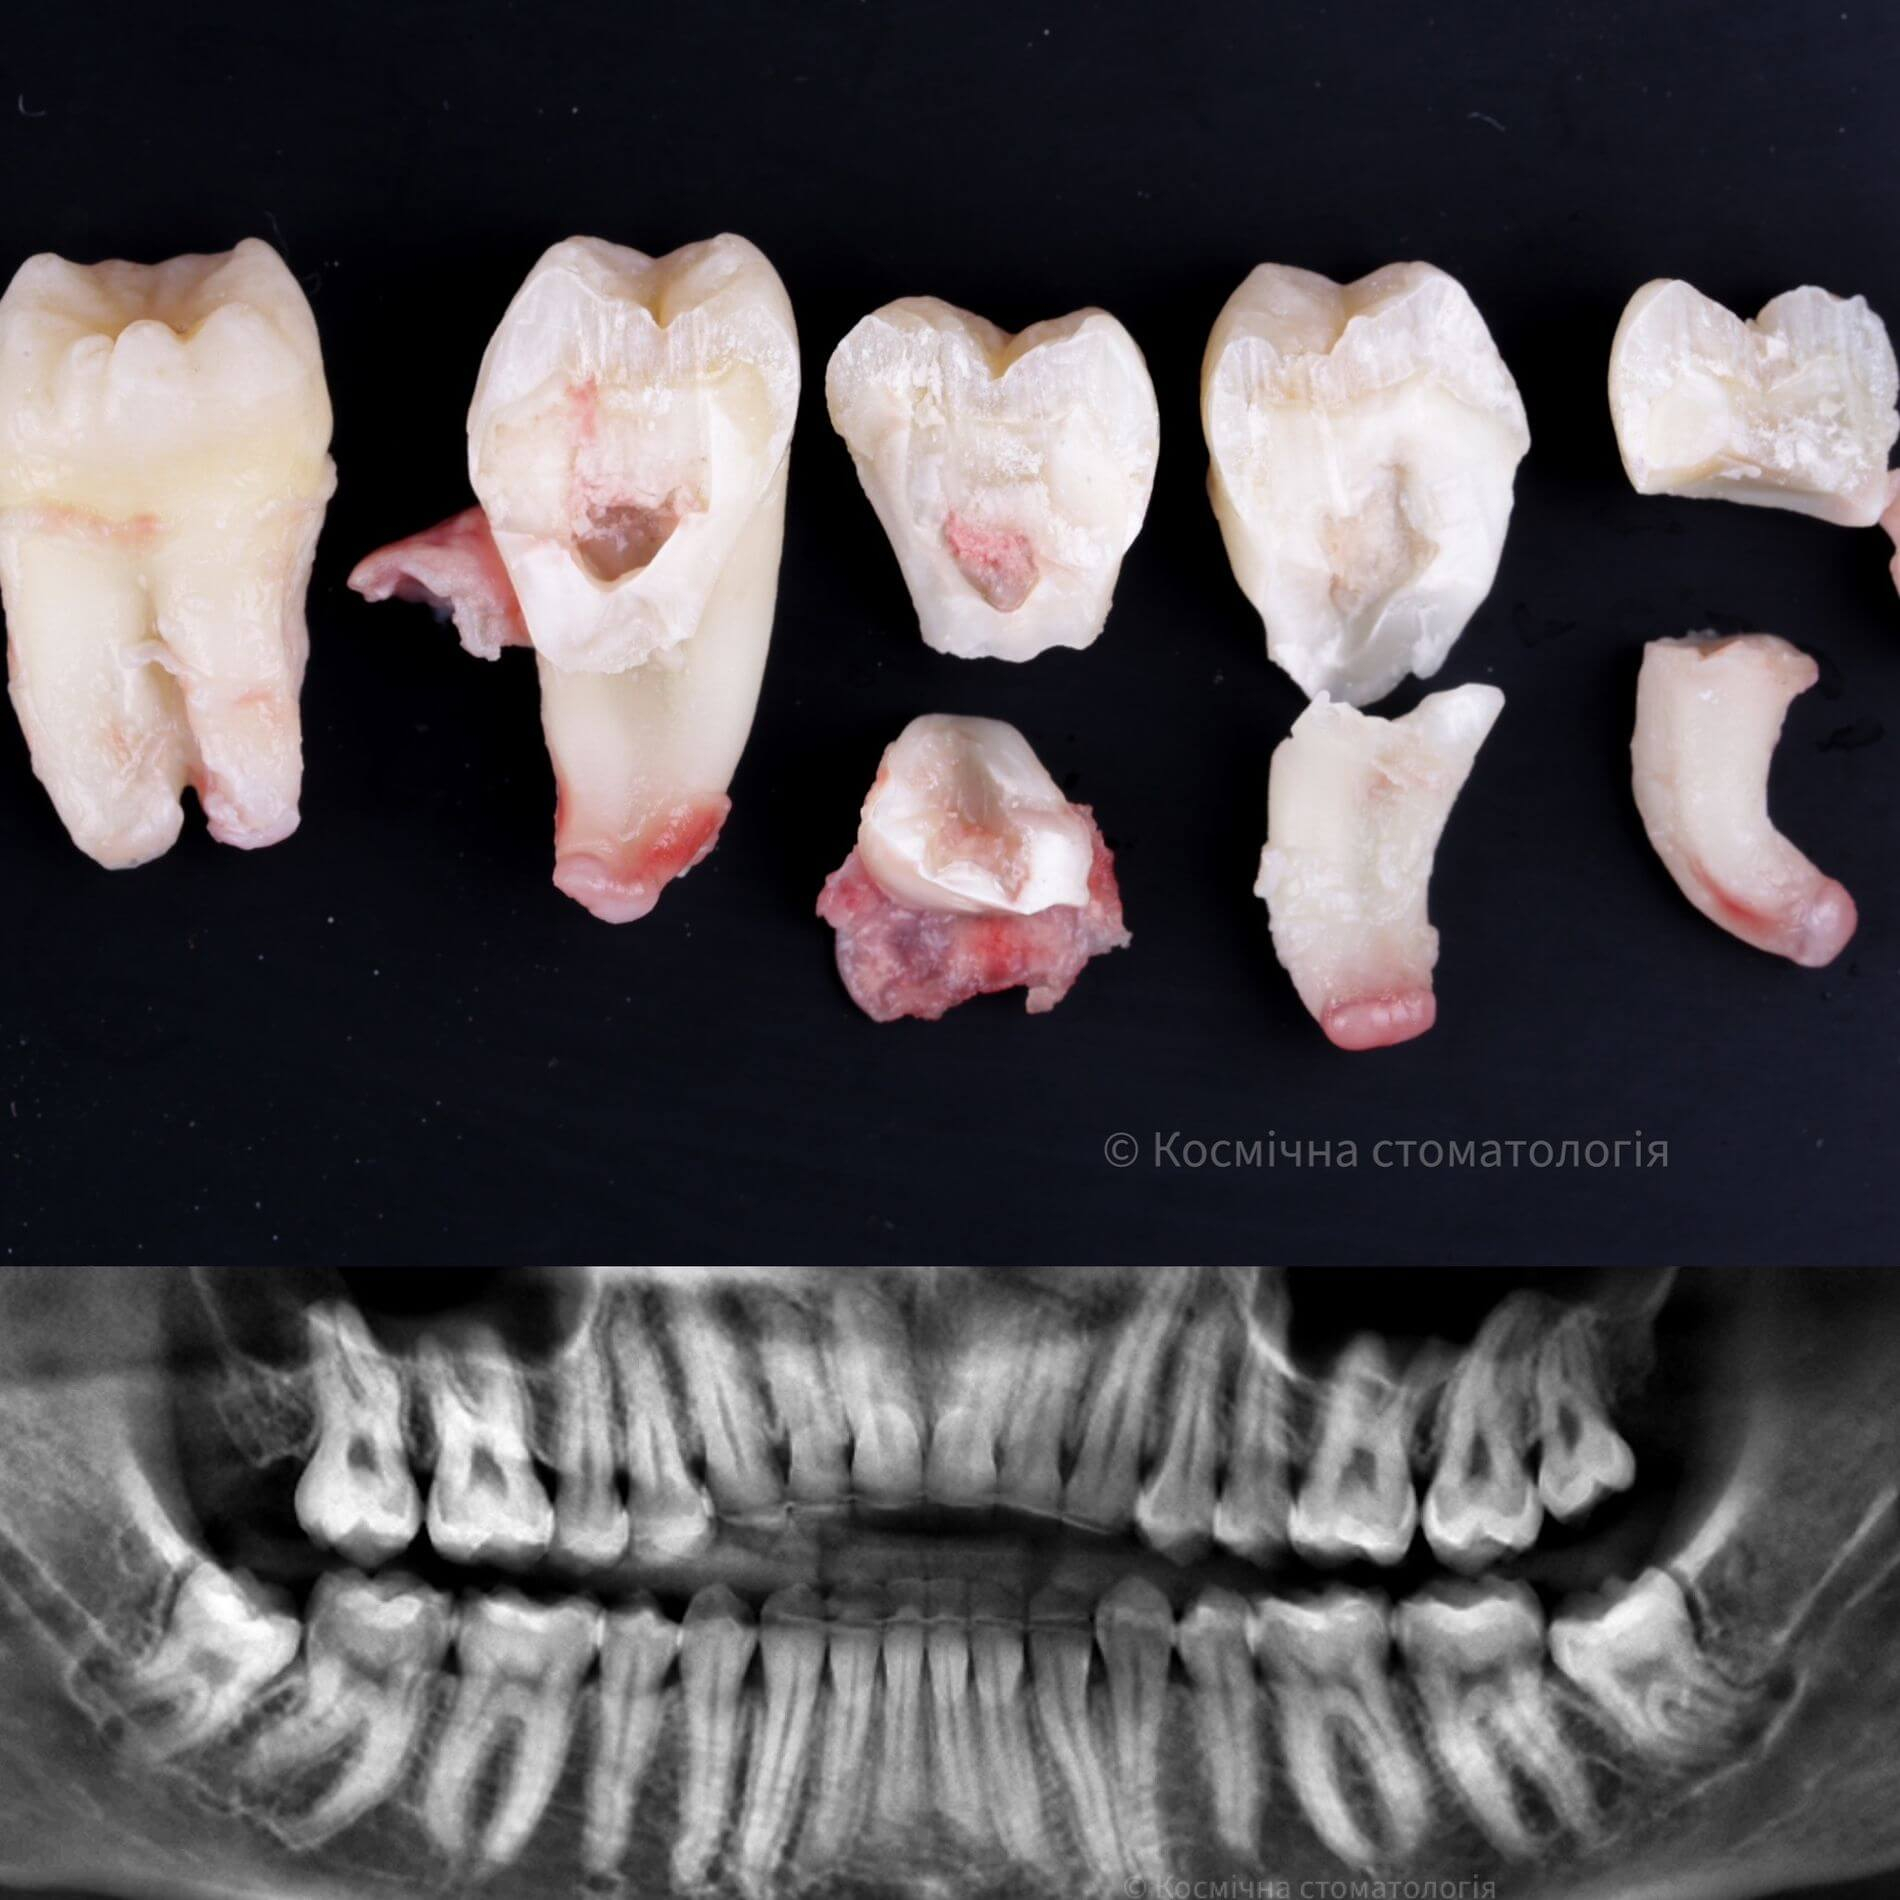

• Полное удаление зуба - если зуб полностью прорезался и имеет сросшиеся корни.

• Отдельное удаление коронки зуба и его корней - если зуб прорезан и корни растут по отдельности.

• Удаление зуба по схеме 1 или 2 с разрезом десен - если зуб прорезан частично.

• Разрез десен, освобождение зуба от близлежащей кости ультразвуком и удаление по схеме 1 или 2 - если зуб не прорезался, но беспокоит.

Галерея